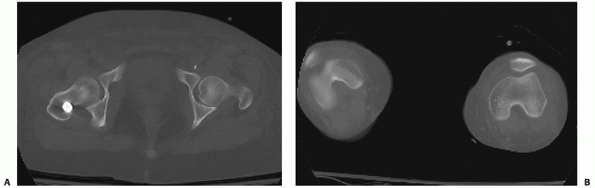

femoral neck. To minimize the incidence of a missed femoral neck

fracture in association with a fracture of the femoral shaft, a number

of additional radiographic evaluations can be considered including an

internal rotation plain radiograph of the hip, a fine-cut (2-mm) CT

scan of the femoral neck, an intraoperative fluoroscopic lateral of the

femoral neck, and postoperative hip radiographs after femoral

stabilization.273